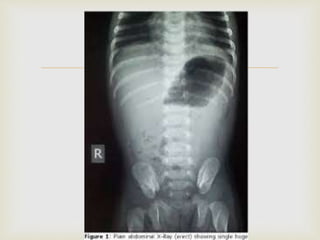

 X ray Abdomen

  Biochemical assessment(pH>7.45,Cl- 3mEq/L)  X ray Abdomen  USG- doughnut sign, pylorus > 4 mm thickness,(normal<2mm) pyloric canal > 14 mm,(normal<10mm) cervix sign on long axis, target sign on short axis. INVESTIGATIONS